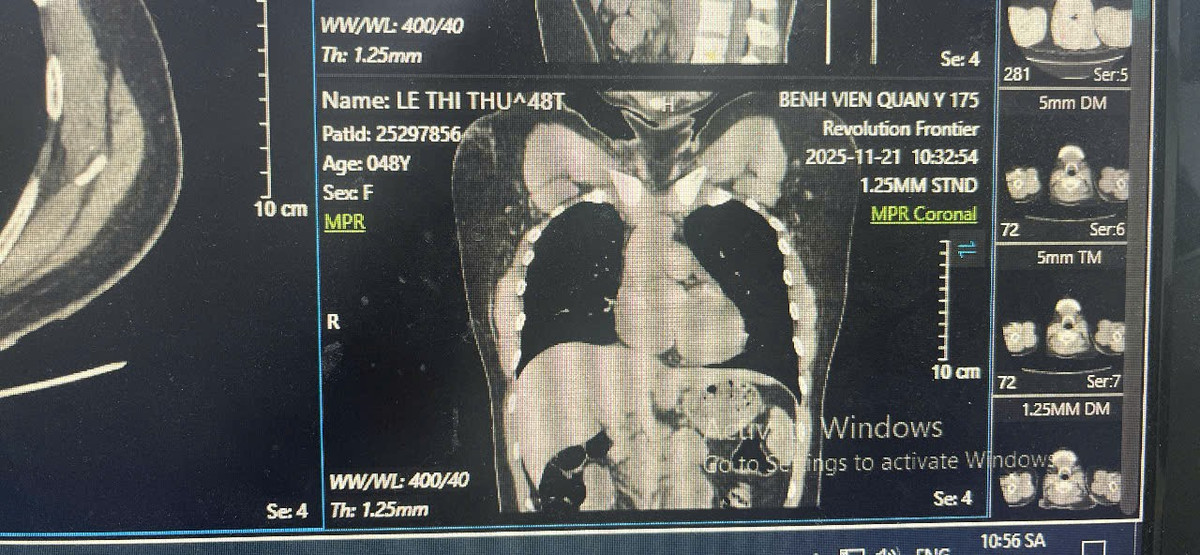

Hình ảnh X quang cho thấy dị vật ở động mạch phổi 2 bên.

Trong lần đi khám tầm soát tại một cơ sở y tế tư nhân, chị được chỉ định chụp CT ngực có tiêm thuốc cản quang, bác sĩ phát hiện hình ảnh một dị vật trong tim, nằm vắt ngang tại vị trí động mạch phổi hai bên.

Sau khi được tư vấn về khả năng cần thực hiện thủ thuật can thiệp lấy dị vật, bệnh nhân quay về bệnh viện đã điều trị ung thư trực tràng để tiếp tục thăm khám và được chụp Xquang ngực.